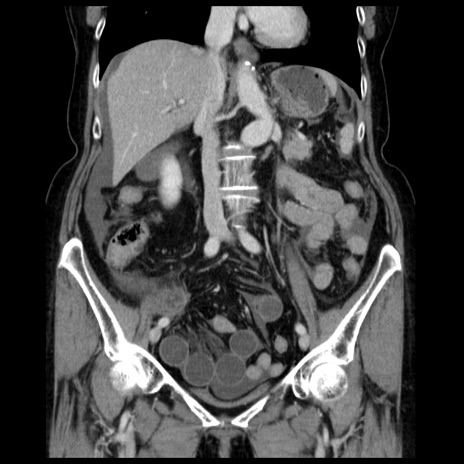

症例13(冠状断像)

【症例】70歳代女性

【主訴】腹痛、嘔吐

【現病歴】15時間程前(昨晩)より腹痛あり。今朝になっても症状の改善なく、嘔吐あり。腹痛も増悪あり、救急外来受診。

【既往歴】子宮癌全摘術後

【身体所見】意識清明、BP 121/72mmHg、P 74bpm、SpO2 100%(RA)、腹部:平坦・軟、腸雑音ほぼ聴取せず。下腹部・心窩部・臍左上に圧痛あり。反跳痛なし。

【データ】WBC 10600、CRP 0.15

横断像